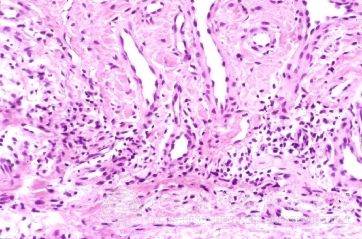

北京京城皮肤医院指出,生殖部位疱疹是一种由单纯疱疹病毒侵犯生殖器皮肤、黏膜引起的红斑、水疱、糜烂、溃疡性损害的性传播性疾病,为了避免生殖部位疱疹给我们带来的影响,一定要避免生殖部位疱疹的病因。如果被感染,要到正规医院接受治疗。